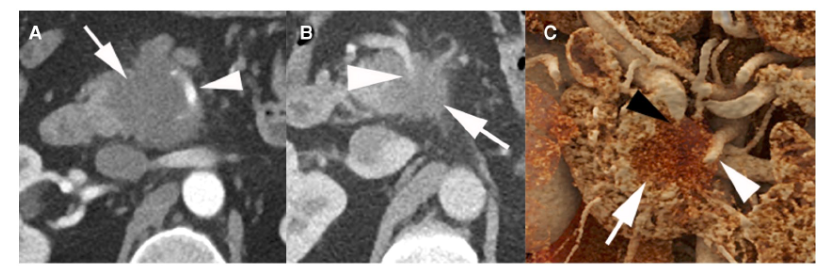

图2:1例50岁男性局部晚期PDAC影像学资料

NCCN指南根据局限性PDAC的术前影像学表现的可切除性分为可切除、临界可切除和局部晚期病变(表3)。肿瘤侵犯动脉未超过周径的180度被认为临界可切除,而超过180度通常被认为局部进展(除了下述的例外)(图2)。肿瘤与静脉临近、包绕静脉或血栓形成,但静脉段可重建,均为临界可切除。不可重建的静脉受累认为是局部进展。NCCN指南与其他指南有许多相同建议,除了肿瘤腹主动脉包绕(>180度)的情况例外(表4)。胰体或胰尾肿瘤伴腹腔动脉包绕,但未累及主动脉或胃十二指肠动脉为临界可切除,采用改良Appleby手术(图3)。然而,在其他指南中,存在腹腔动脉包绕被认为是不可切除的。